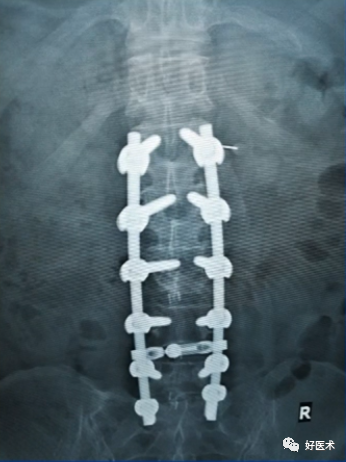

2)置入椎弓根螺钉并发症

①螺钉的长度不够(增加螺钉长度、拧入深度增加);

②螺钉过长(更换短螺钉、拧出螺钉);

③螺钉植入时发生位移(不能接受时退出螺钉,寻找原钉道再次拧入);

④多枚定向螺钉外展角度差别显著(适当更换部分定向为万向螺钉);

⑦置入螺钉后再次透视正侧位,确定螺钉的安全性。